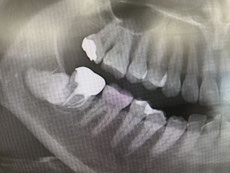

金属はレントゲンで撮影すると真っ白く写るので、

金属の下の虫歯の発見が困難で、手遅れになる可能性があります

セラミックれあればレントゲンで観察可能なので手遅れになる可能性は限りなくゼロにすることができます